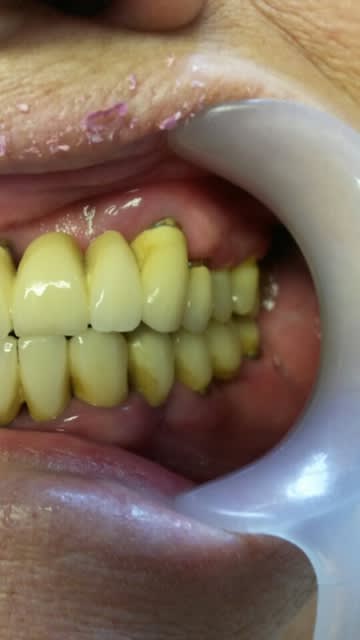

Je soumets un cas à vos critiques ( la prothèse d'usage ne remplacera pas les deuxièmes molaires car la patiente refuse les greffes )

Vu le manque d'hygiène de la patiente, j'espère que tu l'as bien briefé :) Le bas est prévu pour quand ?

ça fait deux mois que je la suis et tente d'améliorer son hygiene ( h2o2 + bicar), diminution du tabac , détartrage.

Les "tout sur 6" fonctionnent très bien avec des extensions raisonnables. 5-8 mm. Perso, je penses que tu sécurise plus ton esprit que le patient. Prothèse plus complexe, contrôle de plaque hyper compliquée, coût très augmenté, je suis pas du tout convaincu mais tu ne fais pas d'erreur et personne ne peut te reprocher ton choix.